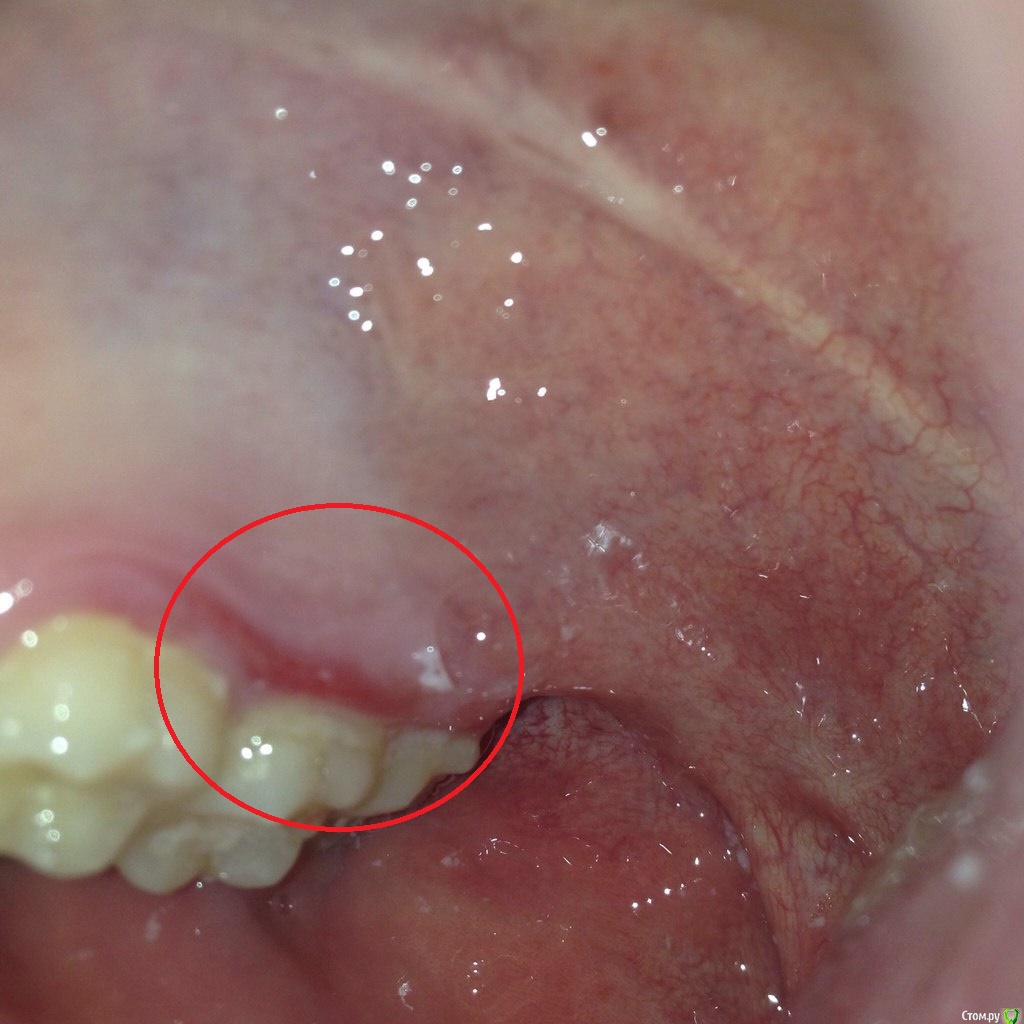

impreZe Опубликовано 26 августа, 2015 Поделиться Опубликовано 26 августа, 2015 (изменено) Доброго времени суток!23.08.15 съел кусок горячего шашлыка (прямо с мангала), после чего почувствовал дискомфорт в районе верхней десны (ранее такого не было), обнаружил тонкую красную полоску, сейчас она теряет цвет.Не подскажите, ожог ли это или мне идти к стоматологу? Изменено 26 августа, 2015 пользователем impreZe Ссылка на комментарий

Bier Опубликовано 28 августа, 2015 Поделиться Опубликовано 28 августа, 2015 гингивит от зубных отложений. К пародонтологу Вам нужно зайти. Ссылка на комментарий